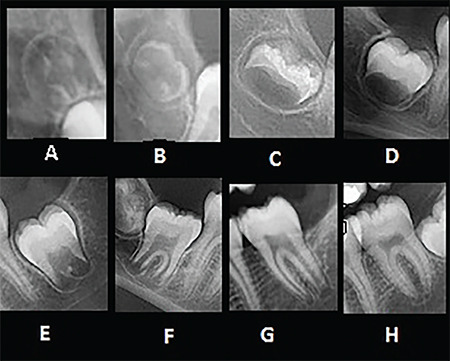

Methods: This retrospective study was conducted on panoramic and lateral cephalometric images of 406 female patients aged 9-14 years. The skeletal maturity and calcification stages of the mandibular canines, first premolars, second premolars, and second molars were determined using the Hassel-Farman and Demirjian (DI) methods, respectively. The prediction accuracy of the peak pubertal stage with the studied teeth was assessed using a receiver operating characteristic curve and the area under the curve (AUC). The DI stage of H was designated as the reference level, and Bayesian logistic regression analysis was used to assess the coinciding chance of each DI stage and peak pubertal stage.